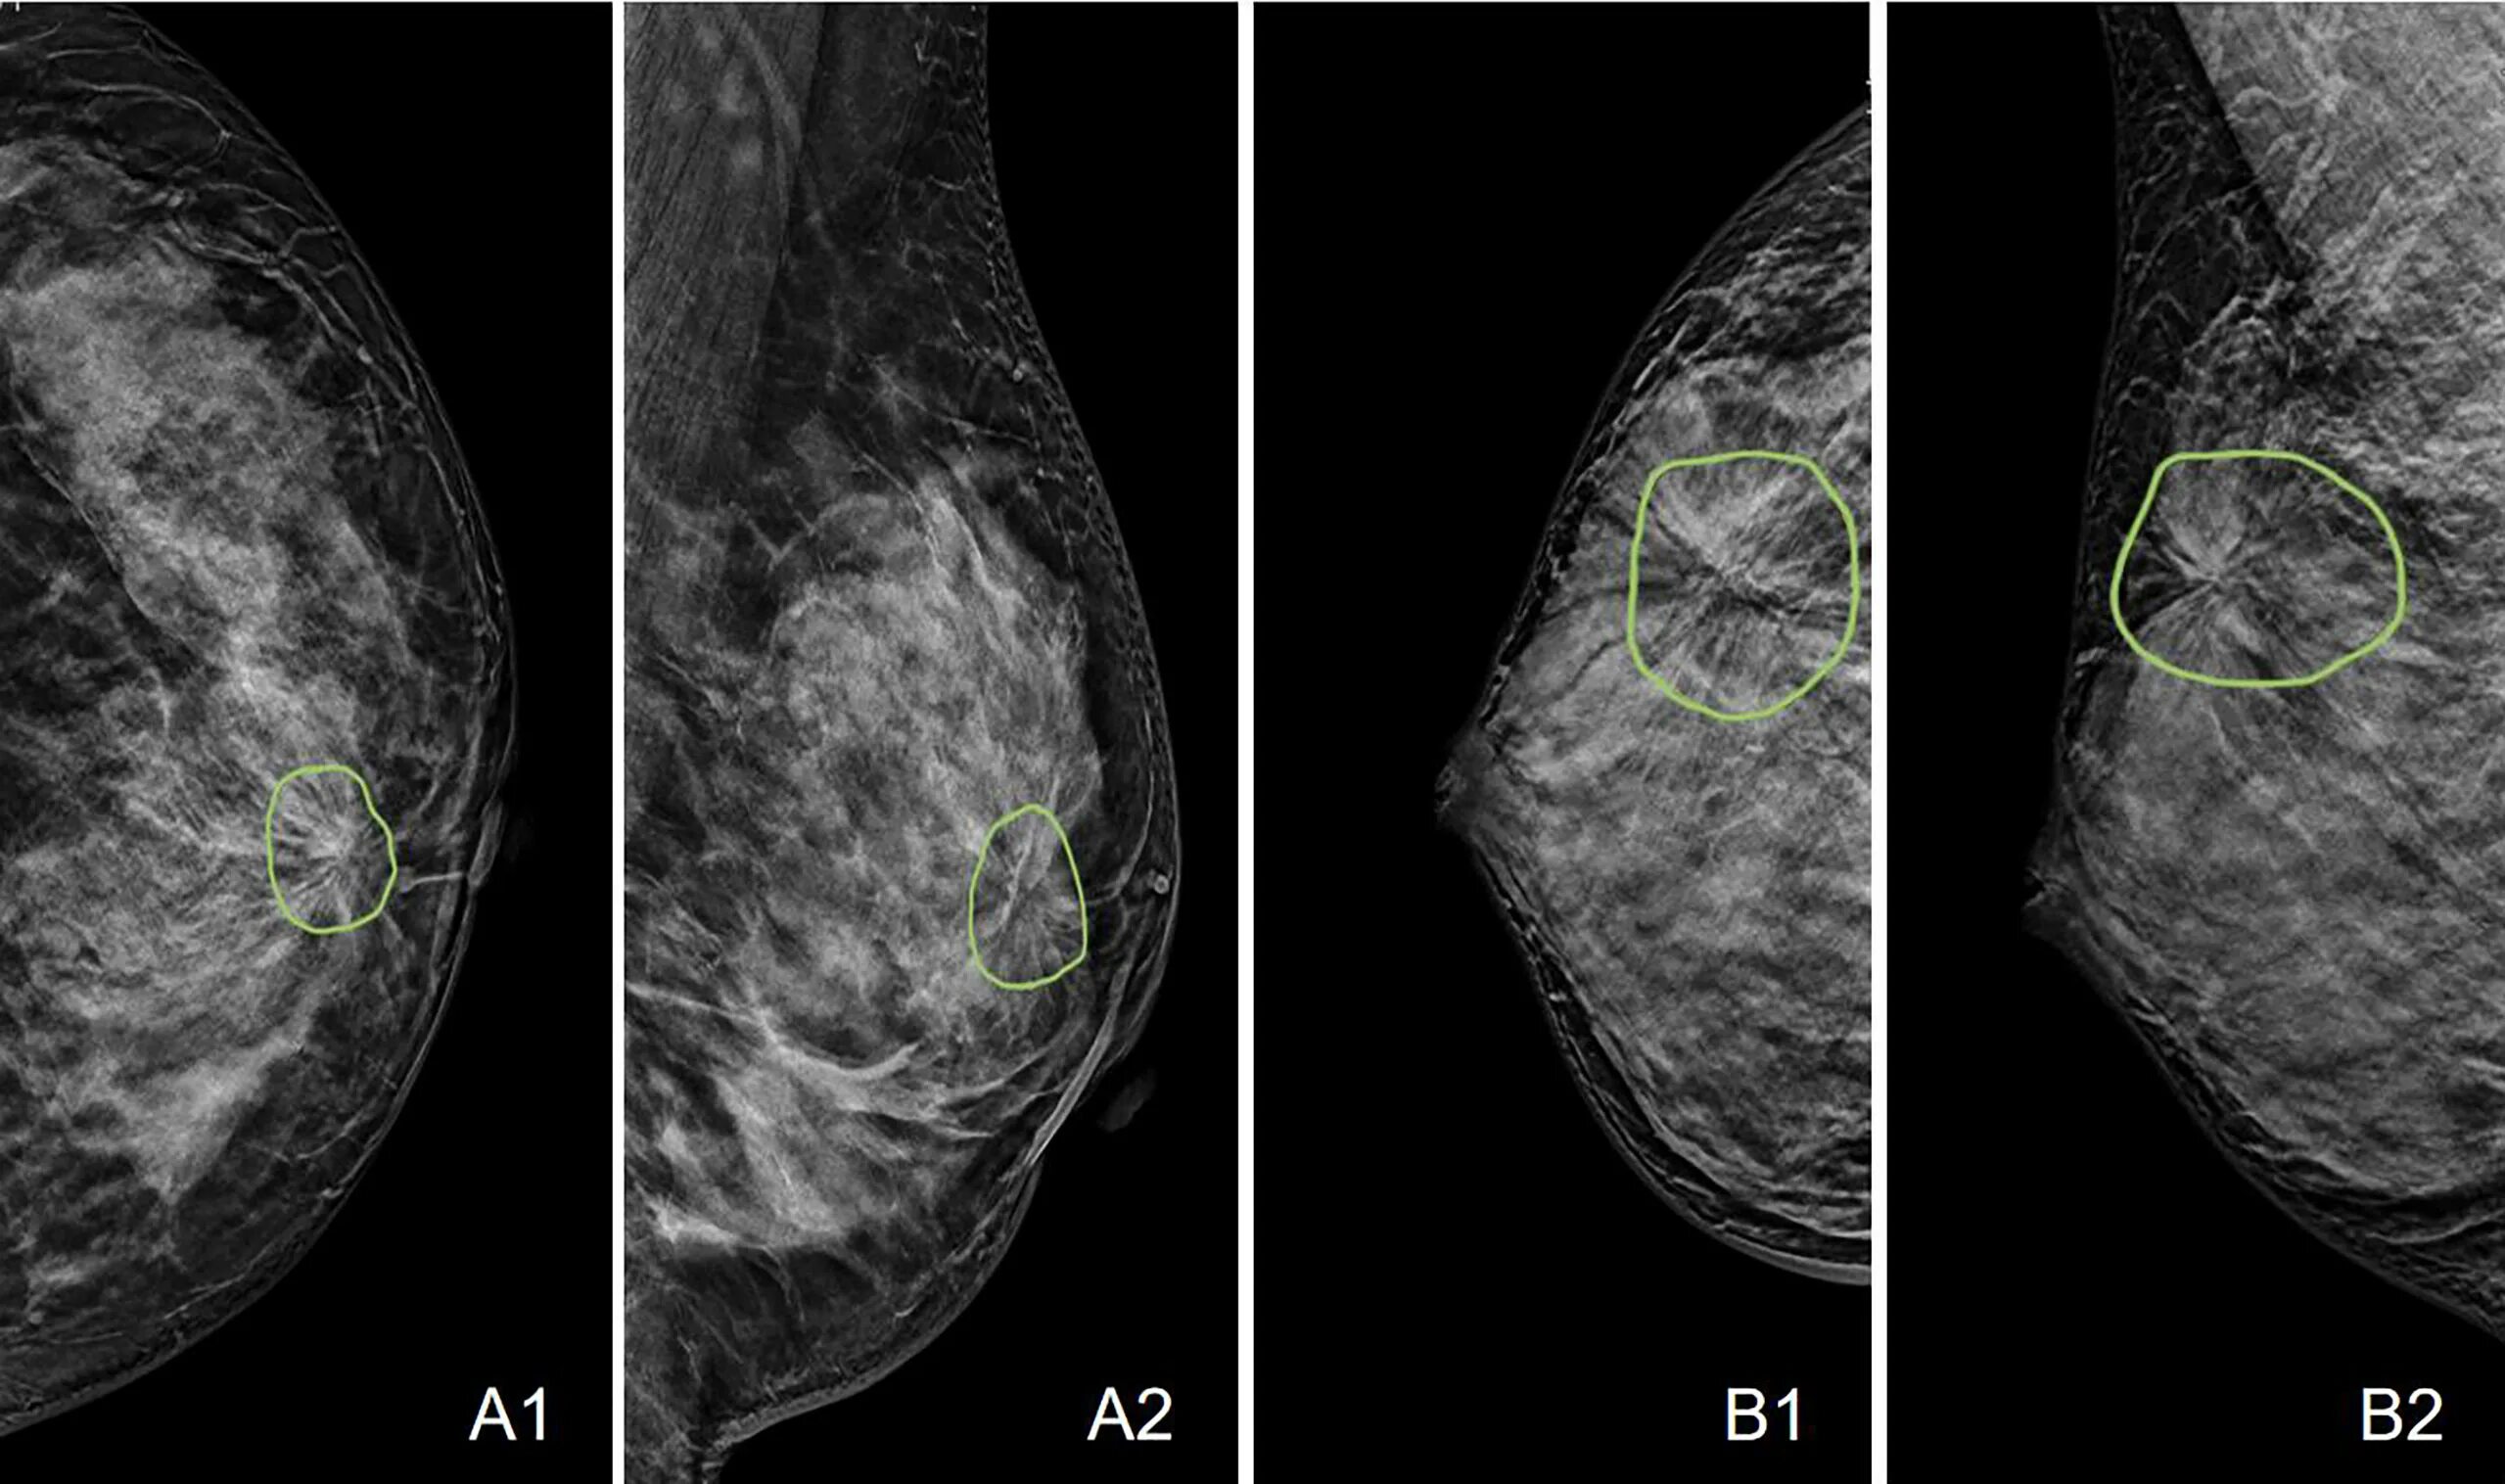

Выраженный диффузный фиброаденоматоз молочных